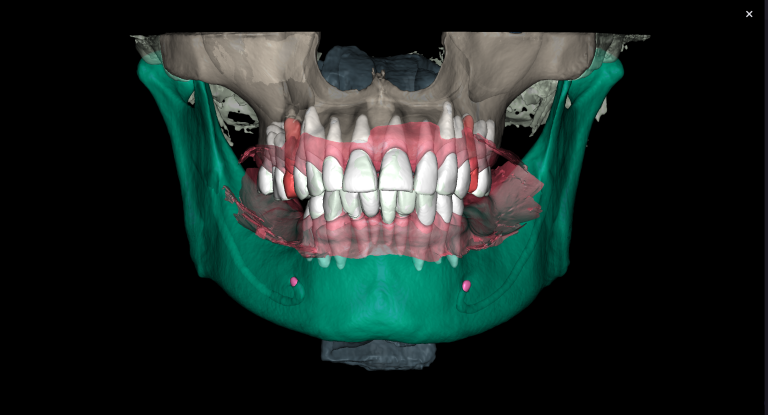

Objective: To reduce the amount of time taken to create a treatment plan for eliners. Problem: When planning tooth movements, the orthodontist needs a significant amount of time to evaluate the clinical case and perform calculations to achieve the most functional and accurate final tooth position.

Solution: Diagnocat’s reports, based on CBCT and intraoral scans (STL files), help the clinician to quickly and accurately make decisions about treatment tactics and final tooth position, and to plan comprehensive treatment according to the individual needs of the patient